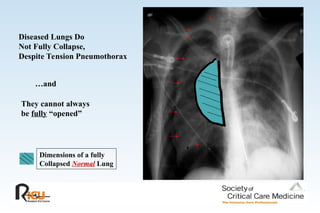

Diseased Lungs Do

Not Fully Collapse,

Despite Tension Pneumothorax

…and

They cannot always

be fully “opened”

Dimensions of a fully

Collapsed Normal Lung